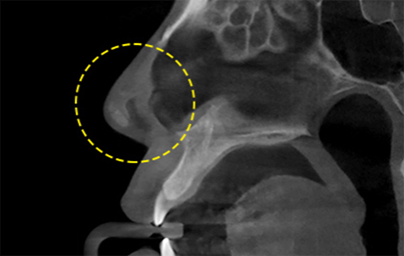

透過立體的骨骼圖進行精準診斷的 3D CT